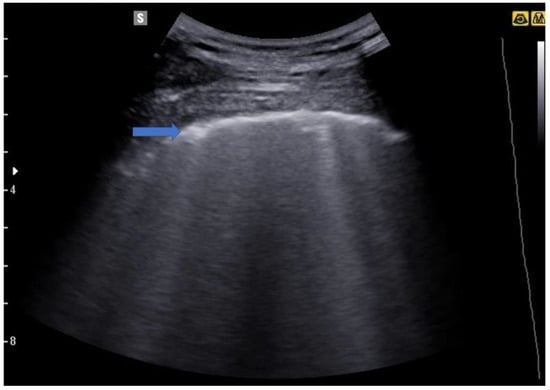

4. Lung Ultrasound on Physiological Lung